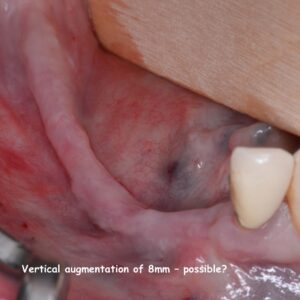

- Horizontal and vertical augmentation with allogeneic bone plates

- Extreme cases – where are the limits?